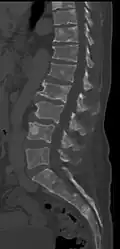

The diagnostic examination of a person with suspected multiple myeloma typically includes a skeletal survey. This is a series of X-rays of the skull, axial skeleton, and proximal long bones. Myeloma activity sometimes appears as "lytic lesions" (with local disappearance of normal bone due to resorption) or as "punched-out lesions" on the skull X-ray ("raindrop skull"). Lesions may also be sclerotic, which is seen as radiodense.[76] Overall, the radiodensity of myeloma is between −30 and 120 Hounsfield units (HU).[77] Magnetic resonance imaging is more sensitive than simple X-rays in the detection of lytic lesions. An MRI may supersede a skeletal survey, especially when vertebral disease is suspected. Occasionally, a CT scan is performed to measure the size of soft-tissue plasmacytomas. Nuclear Medicine Bone scans are typically not of any additional value in the workup of people with myeloma (no new bone formation; lytic lesions not well visualized on nuclear bone scan).

Pathological fracture of the lumbar spine due to multiple myeloma -

CT scan of the lower vertebral column in a man with multiple myeloma, showing multiple osteoblastic lesions: These are more radiodense (brighter in this image) than the surrounding cancellous bone, in contrast to osteolytic lesions, which are less radiodense. -